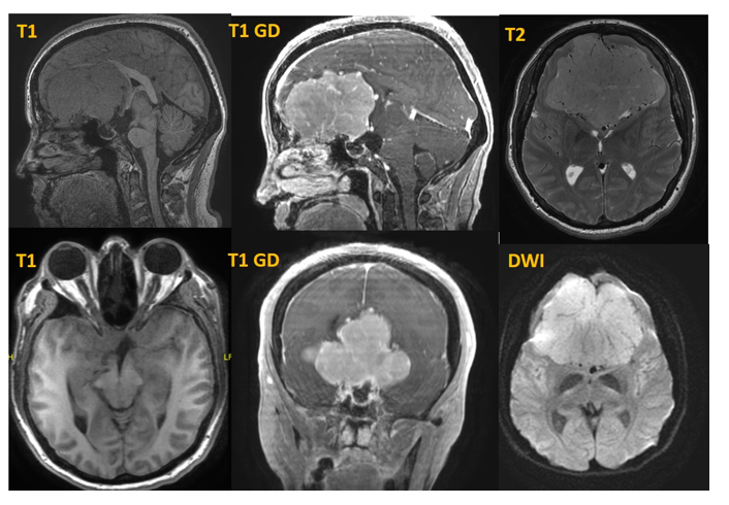

Los meningiomas de surco olfatorio sintomáticos deben ser tratados quirúrgicamente con el objetivo de obtener una resección radical. A nuestra paciente se le ha realizado una resección parcial por vía bifrontal (Figura 3 TC cabeza realizado a los 4 meses).

Figura 3. TC cabeza sin y tras contraste iv.